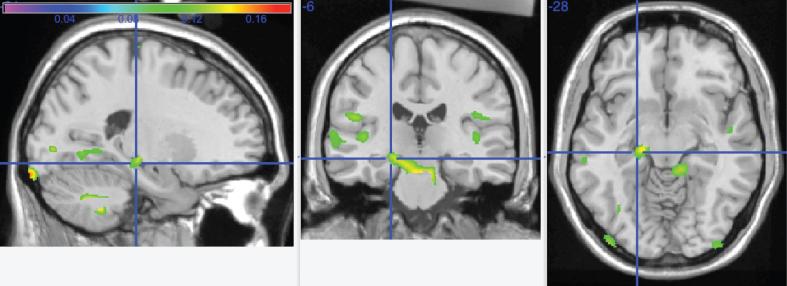

Higher energy output, from a variety of physical activity types, was associated with larger GM volumes in frontal, temporal, and parietal lobes, as well as hippocampus, thalamus, and basal ganglia. High levels of caloric expenditure moderated neurodegeneration-associated volume loss in the precuneus, posterior cingulate, and cerebellar vermis.

来自各种身体活动类型的较高能量输出与额叶、颞叶、顶叶以及海马体、丘脑和基底神经节中较大的GM体积相关。高热量消耗水平减轻了楔前叶、后扣带回和小脑蚓部与神经退行性变相关的体积损失。